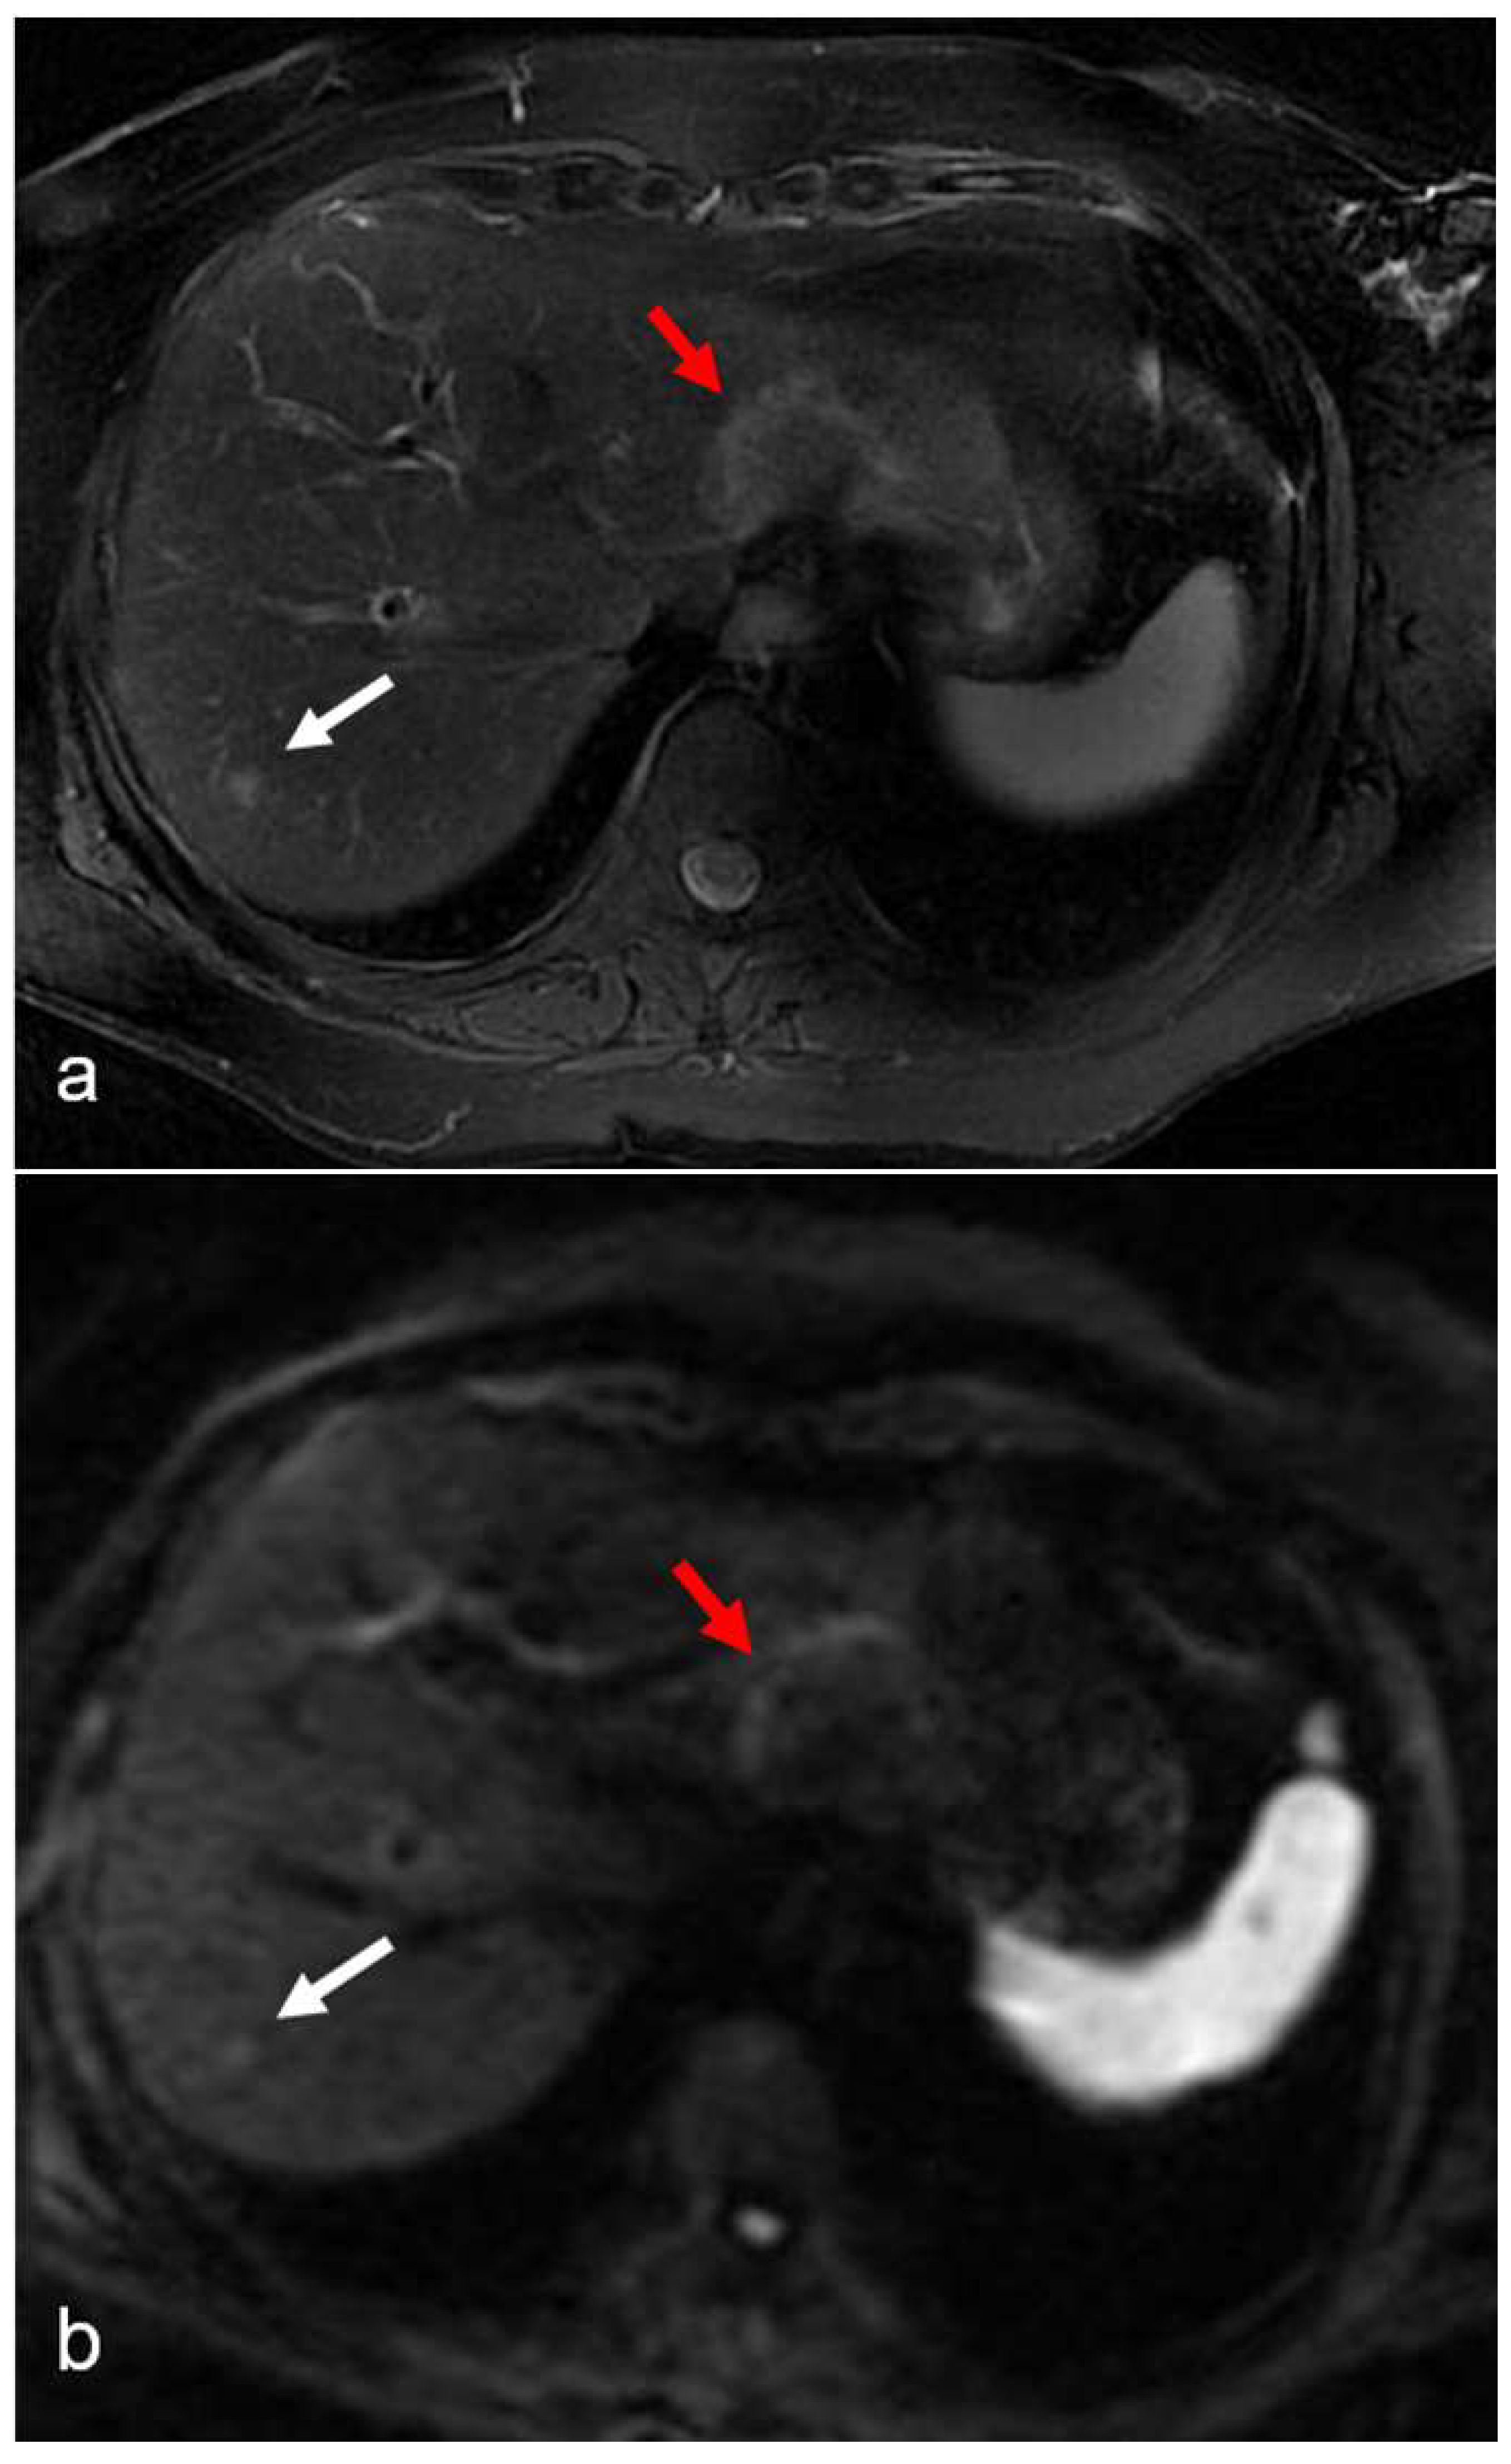

Figure 4.

(a–e) A 62-year-old woman with hepatic metastases from rectal cancer undergoing neo-adjuvant chemotherapy with folinic acid, 5-fluorouracil, and oxaliplatin (FOLFOX). After chemotherapy, a new centimetric lesion appeared in segment 6 (arrow). The lesion was not appreciable on the T2-weighted image (a) and on the DW-MRI image, with b-values of 1000 s/mm2 (b) and an ADC value = 1.25 × 10−3 mm2/s in the reconstructed ADC map (c). After the administration of Gd-EOB-DTPA, a lesion with strong central enhancement and hypointense periphery was identified in the arterial phase image (d) but was no longer recognizable in the hepatobiliary phase image (e). The findings are consistent with a pseudotumor lesion. In the hepatobiliary phase image (e), diffuse hepatic reticular hypointensity of the surrounding liver parenchyma is also appreciably suggestive of SOS.